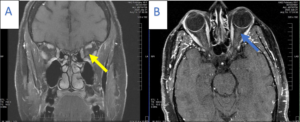

The patient was lost to follow-up but presented again 7 years later complaining of similar painful vision loss, this time in the left eye, for 1 to 2 weeks. Her entering visual acuity was 20/20 OD and 20/60 OS with a 1+ RAPD in the left eye. Entrance testing was otherwise unremarkable. Slit lamp examination was also unremarkable. IOP measured 19 mmHg in the right eye and 18 mmHg in the left eye. Dilated fundus examination revealed generalized optic disc pallor in the right eye. The pallor corresponded to the patient’s history of ON. Examination of the left eye revealed an edematous and hyperemic optic nerve. Cup to disc ratios were stable compared with previous exams. OCT raster scans showed a flat optic nerve in the right eye and nasal elevation and edema of the left optic nerve (Figure 6). Optic nerve head OCT of the right eye showed advanced, generalized thinning of both the GCC and RNFL (Figure 7). This correlated with the patient’s history of ON and her optic nerve presentation (pallor). Optic nerve head OCT scanning of the left eye revealed significant RNFL thickening combined with an inferior-temporal zone of GCC thinning (Figure 7). A recurrence of ON was suspected and repeat MRI of the brain and orbits was performed with and without contrast. The results were essentially normal with patchy, longitudinal enhancement of the left intraorbital segment of the optic nerve (Figure 8). AQP4-IgG and myelin oligodendrocyte glycoprotein (MOG) antibody testing was performed and showed positive anti-MOG titers. A diagnosis of MOGAD ON was established and the patient was treated with pulsed intravenous methylprednisolone followed by an oral prednisone taper. Follow-up visits showed rapid improvement of vision to 20/25 in the left eye in the presence of resultant disc pallor. No RAPD was noted. Repeat OCT showed stable findings of advanced and generalized thinning of both the GCC and RNFL in the right eye. OCT of the left eye showed advanced and generalized thinning of both the GCC and RNFL, which corresponded to the new disc pallor (Figure 9). In the next 2 years, the patient experienced several episodes of ON involving both the right and left eye. With each relapse, she reported rapid vision improvement following treatment with intravenous steroids. She was subsequently placed on maintenance therapy with oral MMF and her condition has remained stable with no further recurrences.

![]() Figure 8. A: T1-weighted coronal magnetic resonance imaging (MRI) with gadolinium showing mild enhancement of the left optic nerve (yellow arrow). B: T1-weighted axial MRI showing mild longitudinal enhancement of the left optic nerve (blue arrow). Click to enlarge |